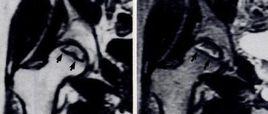

【表現】在股骨頭缺血壞死的MRI表現中,T2WI骨髓腔內,包圍骨壞死灶的低信號帶內側出現平行排列的高信號帶,形似“雙線”。

【解釋】1987年Mitchell等描述所謂“雙線征”(double-line sign),即在T2WI SE序列,包圍骨壞死灶的低信號帶內側出現高信號帶。“雙線征”被認為代表活骨與死骨反應界面,低信號帶代表硬化骨,高信號帶代表肉芽組織。其出現率達80%。雖然有學者認為“化學位移偽影”在“雙線征”中可能扮演重要角色,但大多數學者公認“雙線征”是ANFH較為特異的徵象。?